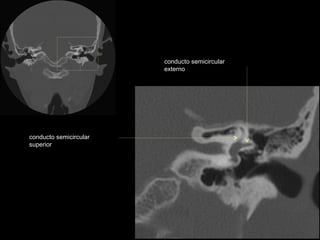

conducto semicircular externo

nervio facial

articulación yunque/martillo

conducto auditivo interno

conducto semicircular posterior

antro mastoideo

celdillas retrolaberínticas

conducto semicircular

superior

conducto semicircular superior

externo